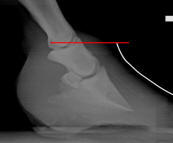

Auburn Study: Caudal Foot Evaluation

Predictive modeling of the equine heel

Recently it has been proposed that healthy soft tissue structures of the equine heel play a primary role in equine soundness. Historically, little attention has been given to the significance of the health of the equine heel soft tissue structures, which are uniquely positioned so as to provide support and protection to the navicular apparatus. More